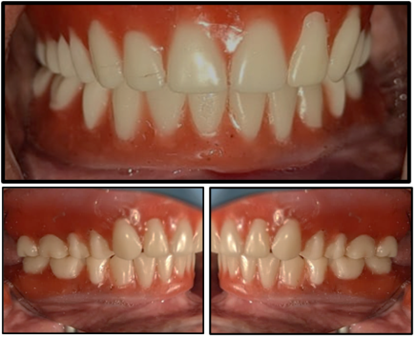

Figure 12: Try In.